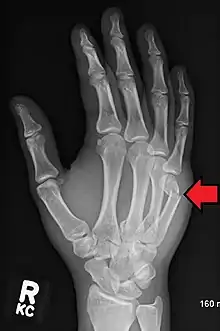

| Boxer's fracture of the 5th metacarpal head from punching a wall | |

A boxer's fracture is the break of the 5th metacarpal bones of the hand near the knuckle.[4] Occasionally it is used to refer to fractures of the 4th metacarpal as well.[1] Symptoms include pain and a depressed knuckle.[2]

Diagnosis by a doctor's examination is the most common, often confirmed by x-rays. X-ray is used to display the fracture and the angulations of the fracture. A CT scan may be done in very rare cases to provide a more detailed picture.